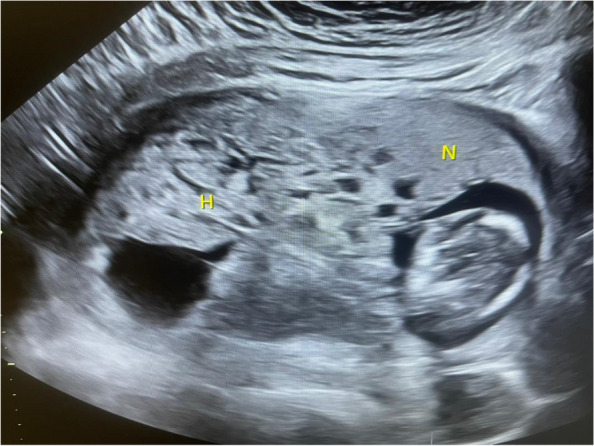

Multiple placental cysts are a common finding in obstetric ultrasound imaging. Although they have benign differential diagnoses, such as hydropic degeneration of the placenta or placental mesenchymal dysplasia, it's important to consider significant pathologies, such as benign gestational trophoblastic disease or hydatidiform mole. A challenging issue in obstetrics is pregnancies with a placenta that has a bipartite texture. This means that one side of the placenta is normal, but the other side is full of cystic formations, and only one fetus is visualized. The main critical concern is the presence of a molar pregnancy because of its catastrophic consequences. Here, we report a rare case in which the gravid uterus had a normal diploid fetus but had a bipartite placenta, which was triploid in the hydropic part, revealing a unique genetic pattern.